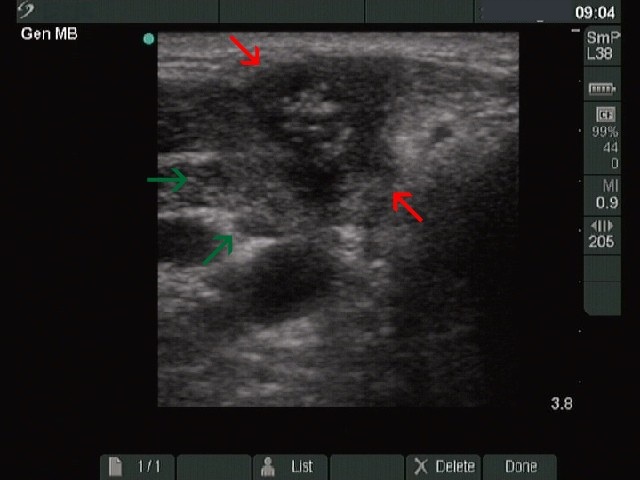

Intranodular hyperechogenic figures - case 1386

(ultrasonographic picture 1a)

Right lobe transverse scan. There is a hypoechogenic inhomogeneous lesion marked with red ventral to the operated thyroid marked with green. The lesion contains a hyperechogenic patch with small bright hyperechogenic granules within it. This pattern is very similar to an amyloid deposit seen in medullary cancer.